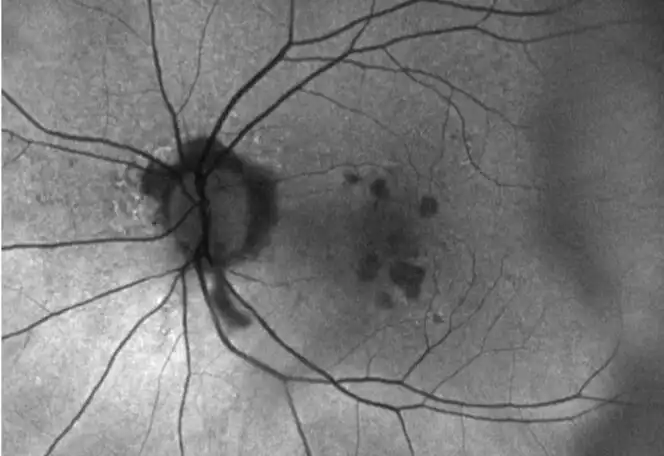

IZERVAY™ (avacincaptad pegol intravitreal solution) is indicated for the treatment of geographic atrophy (GA) secondary to age-related macular degeneration (AMD)